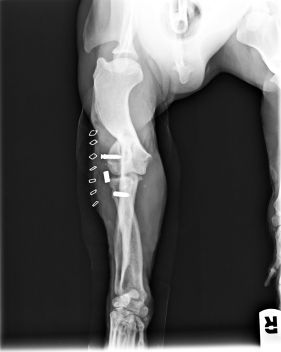

Enseguida nos hicimos cargo de él. Tras pasar una primera revisión veterinaria, decidimos trasladarlo a Madrid a una casa de acogida para tener una segunda opinión de un traumatólogo de nuestra confianza. El resultado fue el diagnóstico de luxación de codo en la pata delantera, y de fractura de huesos con luxación en la pata trasera. El problema es que estas lesiones tenían una antigüedad de unas 5 semanas, por lo que ya se había empezado a formar fibrosis y callo. Con todo ello se decidió dejar que la fractura siguiese su consolidación, y operar la luxación de codo, para intentar que recuperase completamente su funcionalidad.

Como se puede ver en las radiografías, con dos cirugías sobre la articulación, se consiguió la perfecta recolocación.